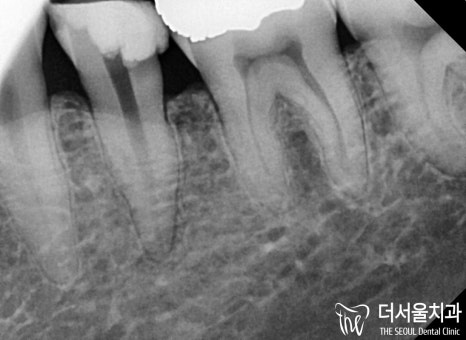

치수까지 감염이 진행되었으며

심한 통증을 느끼고 있던 환자분,

이런 경우에는 임플란트나 신경치료를 통해

치료를 할 수 있는데요.

다행히 환자께서는 이가 심하게 흔들리거나

고름이 잡힐 정도로 심하진 않았습니다.

따라서 자연치아를 살리는 마지막 방법인

신경치료를 통해 문제를 개선하기로 했습니다.

감염이 생긴 곳을 깨끗하게 삭제한 뒤

치과용 충전재를 사용하여

뿌리 끝까지 확실하게 밀폐시켰습니다

이후 병소가 확실하게 잡힌 것을

확인한 뒤에 보철 제작을 돕기로 했는데요.